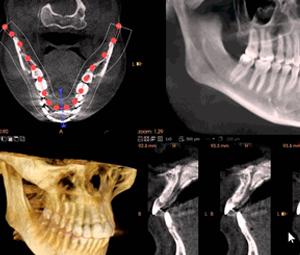

Rentgenologiniai tyrimai yra reikalingi gydymo plano sudarymui prieš implantacijos, sinuso dugno pakėlimo ir kaulo priauginimo, protinių dantų rovimo operacijas, nes pateikia virtualius paciento veido, žandikaulių srities, šaknų skilimų, kaulo lūžių vaizdus. Kompiuterinė tomografija parodo burnos ir aplinkinių audinių trimatį vaizdą (3D), tad ją rekomenduojame daryti pacientams prieš chirurgines procedūras siekiant tiksliai suplanuoti gydymą ir įvertinti kaulo būklę, jo storį, visa tai išanalizuoti trijose plokštumose.

• Tikslu. Kompiuterinė tomografija trimačiu vaizdu pateikia aiškesnį 75 mkm vaizdą, kuris naudojamas endodontijoje šaknies kanalų gydymui. Kompiuterinė tomografija suteikia galimybę įvertinti dantų ir jos audinių būklę iš visų pusių, pašalinami visi iškraipymai. Turint tikslius išmatavimus išvengiama netikslumų implantacijos ir kitų chirurginių operacijų metu, nepažeidžiami nervai ir kraujagyslės, sinuso ertmė.

Kompiuterinė tomografija gali būti įrašoma į laikmeną arba saugoma „PAPADENT“ odontologijos klinikoje. 3D žandikaulio nuotrauka Jums suteiks išsamią informaciją apie kaulo būklę, jo tankį, plotį ir aukštį. Atlikus 3D dantų nuotrauką Jums bus sudarytas išsamus gydymo planas, pagal kurį bus atliekamos procedūros. Lyginant su panoramine dantų nuotrauka, kompiuterinė tomografija parodo visą vaizdą 3D formatu, įvertina svarbias anatomines struktūras, suteikia žymiai daugiau informacijos implantacijai ir kitoms procedūroms.

Visų dantų atkūrimas all-on-4 metodika. Implantacija. Šiuo atveju būtina padaryti 3D kompiuterinę tomografiją. Panoraminė rentgeno nuotrauka yra dvimatė, tai yra ji suteikia informaciją tik apie dvi dimencijas – aukštį ir plotį. Įvertinti, ar jūs esate tinkamas kandidatas dantų implantams, reikia matyti ir kaulo tūrį – būtent tai ir parodo KT nuotrauka.